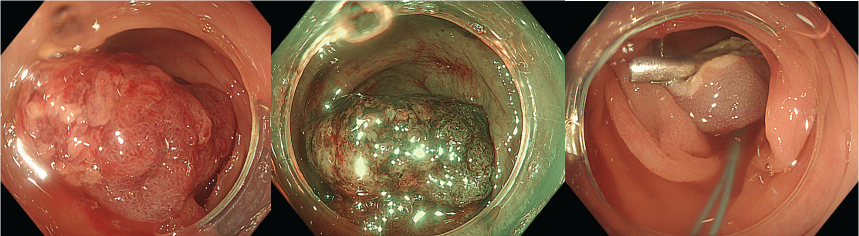

Tiến hành can thiệp ESD

Kết quả, ca can thiệp kéo dài 100 phút, bệnh nhân được can thiệp thành công mà không xảy ra biến chứng gì trong can thiệp.

Kết quả bất ngờ: tổn thương được ESD tại manh tràng ổn định, không thấy điểm chảy máu; nguồn xuất huyết thực sự đến từ một polyp lớn chưa xử trí ở đại tràng sigma. Với sự đồng thuận từ người nhà và bệnh nhân, ekip đã tiến hành can thiệp cắt polyp sử dụng endoloop, vừa điều trị vừa giải quyết triệt để nguyên nhân chảy máu.